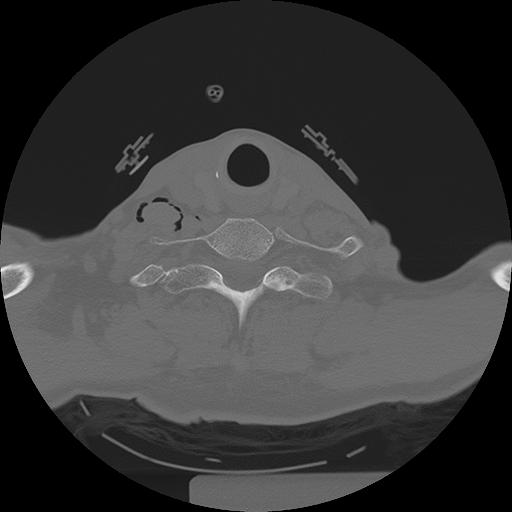

11 HUESO,,Axial,2.0,HUESO,,